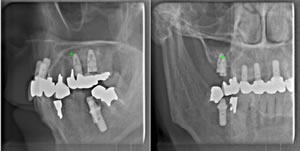

はぎしりを制する者は歯科治療を制する

尊敬するウィーン大学前教授スラバチェック医師の教えです。なぜ、歯を失ったのか?そしてインプラント治療を受けなければならなくなったのか?その答えは夜間のはぎしり・くいしばりにあります。人はストレスを解消するために、ノンレム睡眠時にはぎしり・くいしばりをします。その負荷はなんと体重の3倍にもなります。歯を失って当然です。多くの論文が発表され、今や世界共通のエビデンスとして認識されています。歯周病、虫歯の原因も同じなのです。私たちは、夜間のはぎしりくいしばりを考慮した診断と治療を行っています。

歯を失い、インプラント治療に至った原因に立脚してこそ良い治療ができるのです。

包括的歯科治療こそ最も良い治療です。